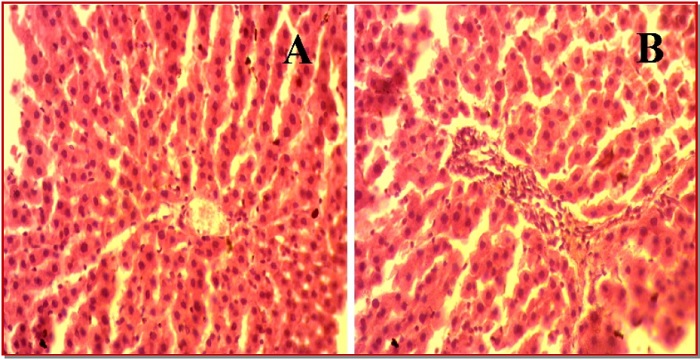

The present study investigates the pathological implications of parenchymal iron overload due to CCl4 treatment in liver dysfunction. Sixteen female rats were randomly divided into control and CCl4 treated groups. The serum levels of tramsaminases, malondialdehyde, advanced protein oxidation product, catalase, and reduced glutathione concentrations in the plasma and hepatic homogenate were determined. Moreover, histopathological changes in liver sections were investigated for inflammatory cell infiltration, fibrosis and iron overload. The administration of CCl4 resulted in increased liver marker enzymes activities and oxidative stress parameters mentioned above compared to control. Moreover, CCl4 administration also decreased antioxidant enzymes activities and increased inflammatory cell infiltration and fibrosis along with iron deposition in liver of rats. These findings indicate that CCl4 may induce hepatic fibrosis and inflammation during CCl4 induced liver injury via iron mediated oxidative damages.